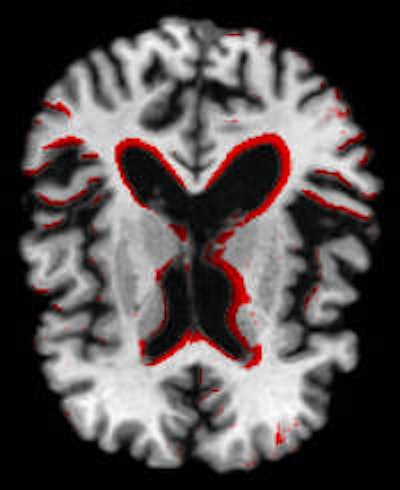

PredictAD aims to extract biomarkers from heterogeneous patient data and integrate them for objective and evidence-based diagnostics. For example its reasearch team is exploring how MRI can be used to measure atrophy in the mediotemporal lobe, which is recognized as a hallmark of Alzheimer's.

To meet this need, the PredictAD team has developed tools for measuring the size of the hippocampus, the atrophy rate of the hippocampus, and two approaches based on comparing patient data with previously diagnosed cases available in large databases. PET is also being studied in the project. A novel tracer developed recently especially for diagnostics of Alzheimer's disease provides promises for very early diagnosis of the disease.